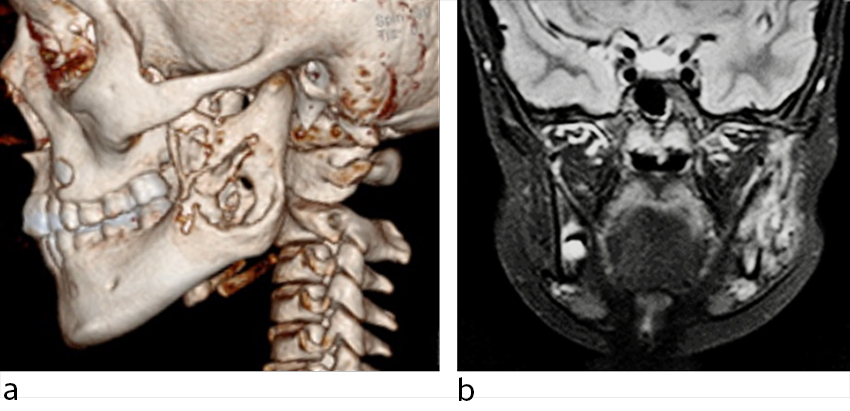

Det ble ikke avdekket tannpatologi ved klinisk undersøkelse, tannrøntgen eller dental panoramarøntgen (ortopantogram, OPG). Antibiotikabehandling med fenoksymetylpenicillin-mikstur 50 mg/mL × 3 (7,5 mL + 7,5 mL + 15 mL) ga tilbakegang av symptomene i løpet av få dager. Nevnte ortopantogram, CT og MR av ansiktsknokler viste omfattende osteolytiske og inflammatoriske lesjoner i venstre underkjeve (figur 1). For å utelukke neoplasi ble det foretatt PET-CT-undersøkelse med fluorodeoksyglukose (FDG), som viste diffust økt FDG-opptak i venstre ramus mandibula.

En jente i barneskolealder ble utredet på grunn av en diffus hevelse over høyre underkjeve. Bortsett fra residiverende ørebetennelser, hadde hun vært frisk. Hevelsen hadde kommet og gått periodevis i et års tid uten ledsagende symptomer. Pasienten hadde ikke hatt feber og var ikke blitt behandlet med antibiotika (figur 2).